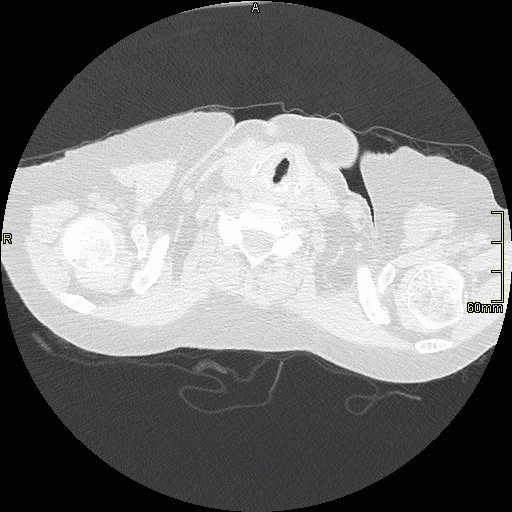

HRCT - Axial Prone Inspiration (Lung Window)